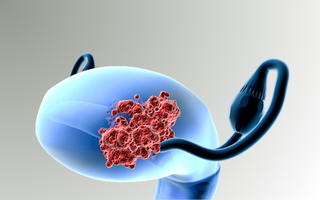

HPV Prevention & Vaccination

The clinic provides the Gardasil vaccine for protection against Human Papillomavirus (HPV), one of the leading causes of cervical cancer and other gynecologic conditions.

The vaccine offers long-term protection and is recommended for girls and women according to approved medical guidelines.